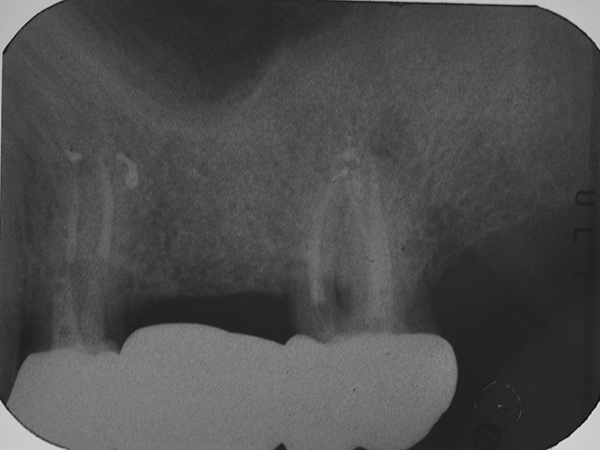

A causa della frattura della radice vestibolare del 24, tramite sondaggio puntiforme e fistola, si è proceduto alla separazione del ponte 24-x-26, conservando l’elemento 26.